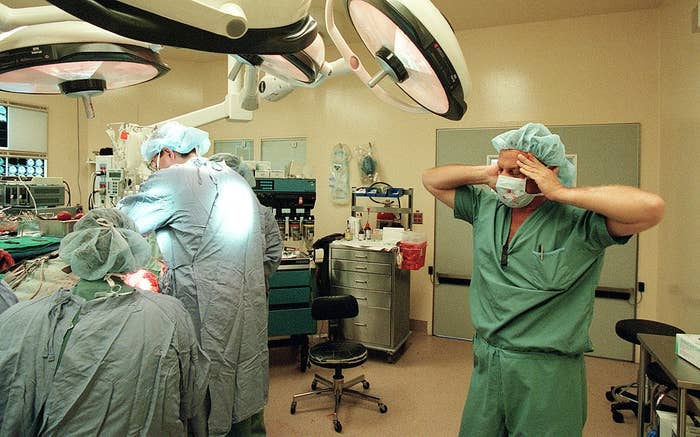

Surgeons, What's The Most Jaw-Dropping Thing You've Seen In The OR?

Be honest, is it actually wilder than Grey’s Anatomy? 👀